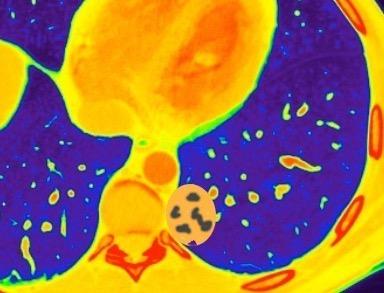

Anillo radiopaco formado por ganglios aumentados. El centro radiotransparente lo constituyen tráquea y bronquios centrales. Más frecuente en Tb y linfoma